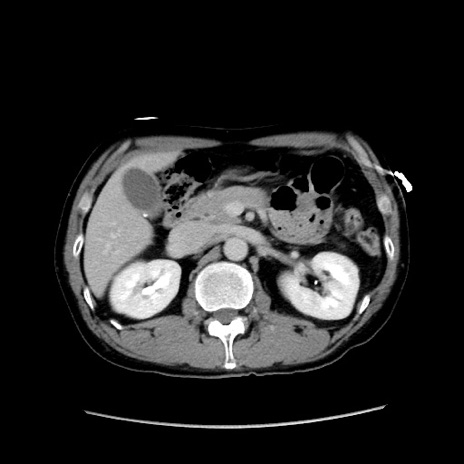

冠状断像

症例37(横断像)

【症例】40歳代 男性

【主訴】腹痛

【現病歴】4時間ほど前に電車に乗車中に臍部上より腹痛出現。徐々に増悪し起立困難となり、救急外来受診。生ものは数日食べていない。今朝お雑煮を食べた。

【身体所見】BT 36.8℃、BP 117/84mmHg、HR 91/min、SpO2 97%、苦悶様、腹部:臍上部広範囲圧痛あり、反跳痛±

【データ】WBC 8100、CRP 0.03